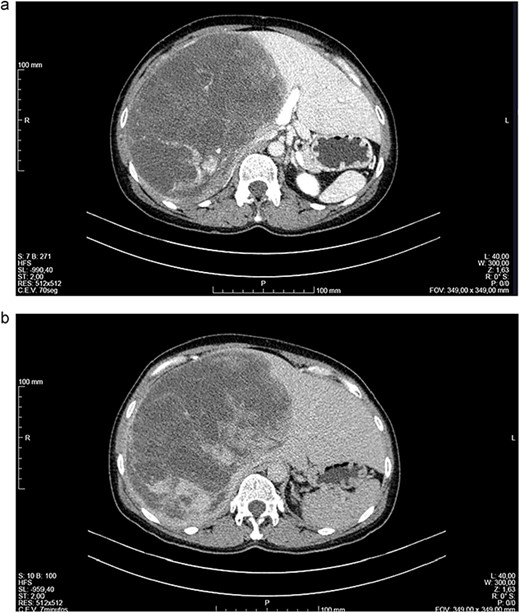

Abdominal CT (Fig. 1a and b) and MRI (Fig. 2a and b) showed a 18 × 12 × 20 cm3 lobulated cystic mass with thin enhancing septa in the right lobe of the liver with fluid levels suggesting atypical hemangioma. The right hepatic vein not dissociable to the tumor (Fig. 2c).

(a, b) Computed tomography (CT) scans of a woman aged 49 years with undifferentiated embryonal sarcoma of the liver. Liver of increased dimensions due to the presence of voluminous oval mass and well-defined limits occupying practically the entire right lobe (measures 16 × 16 × 20 cm3). It is a heterogeneous mass, with areas of apparently liquid spontaneous density. Captures contrast gradually and progressively.